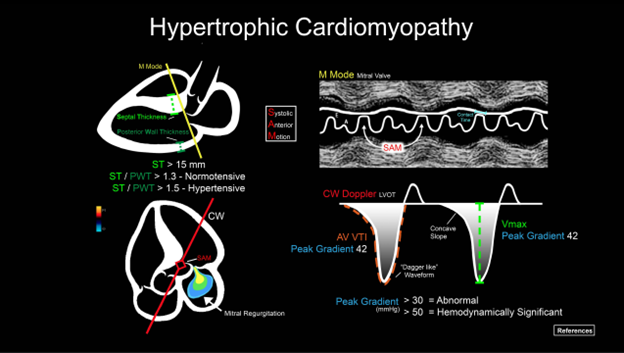

Series

ACEP’s critical care ultrasound subcommittee has been working on advanced cardiac ultrasound educational cards to share with the community as a reference when performing critical care bedside ultrasound. Figure 5 is a graphical representation of HCM and the pathologic measurements. It is a useful tool when discussing a case with your consultants. Stay tuned for more to come from the group!

Figure 5. Illustration of an advanced cardiac ultrasound educational card on aortic stenosis.